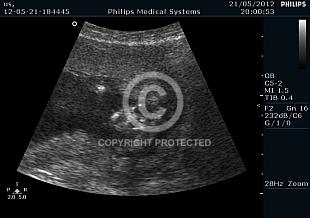

Hydrocephalus

Brain anomalies